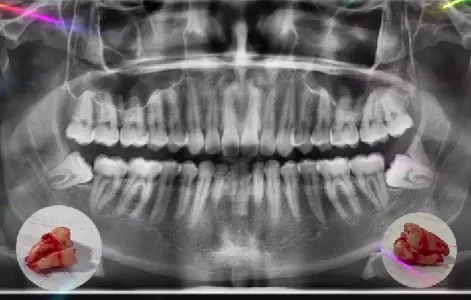

Vemos exactamente dónde están raíces, nervios y posición real.

Confirmamos si realmente necesitas la extracción y qué tan compleja será.

Radiografía panorámica.